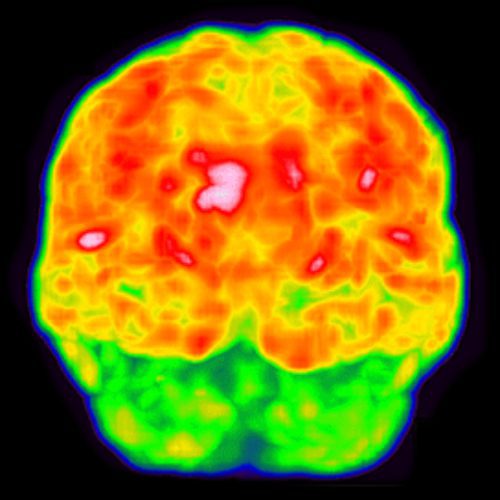

Ejemplos de imágenes de tomografía PET CEREBRAL mostrando metabolismo cerebral.

La tomografía PET CEREBRAL detecta la distribución del FDG en el cerebro, localizando las áreas de disminución ó aumento de la actividad metabólica cerebral de manera precisa y confiable.

• El metabolismo cerebral consume el 25% del total de la glucosa que consume el cuerpo. El FDG ó glucosa radioactiva, permite detectar las áreas del metabolismo normal ó anormal en el cerebro.

• Durante el periodo de relajación el FDG se distribuye en las células cerebrales.

• La mesa mueve al paciente a través del detector de FDG (aproximadamente 10 min).